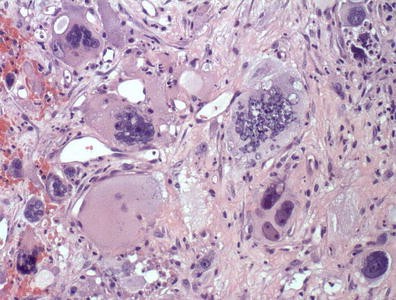

Method: A total of 15 patients with SDHB-mutation were analyzed genomic DNA, clinical data on family history, catecholamine types, tumor metastasis, patient prognosis, and histology of the tumors. Histologic analyses were performed using the new classification named Grading of adrenal pheochromocytoma and paraganglioma (GAPP) classification that was made based on a nationwide Japanese survey. All tumors were scored from 0 to 10 points, and were also graded according to three differentiation types depending on the total score: well (0–2 points), moderate (3–6) and poor (7–10).